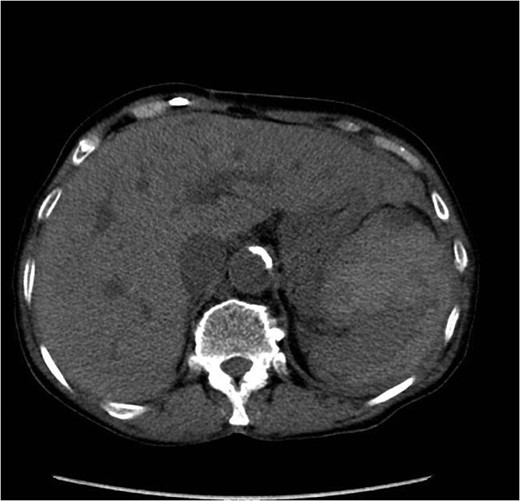

On Day 4, her haemoglobin had decreased to 64 g/dL. Her blood pressure and heart rate remained within normal parameters but a repeat clinical examination revealed a large peri-umbilical ecchymosis (Cullen's sign) (Figs 1 and 2). At this point, she was referred to the surgical team and a computed tomography (CT) scan confirmed a grade V splenic injury with overlying rib fractures, free fluid within the pelvis, but no active bleeding (Figs 3 and 4). The patient's Rivaroxaban was discontinued and Haematology advice was sought. The patient was transfused with packed red blood cells and managed non-operatively. The patient responded well to fluid and blood-product resuscitation, and since discussion with the Radiology team excluded active haemorrhage on the CT non-operative treatment was opted. Concurrent treatment was given for pneumonia and the patient was discharged on the 14th day. Rivaroxaban was re-commenced in the community on discharge following advice from the hospital Haematology team. A 24-h ECG and cardiology follow-up was arranged as an outpatient. Up to the current time of publication, her recovery has been unremarkable.